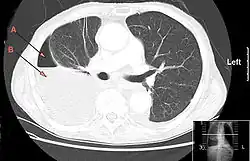

| CT chest showing large right sided hydro-pneumothorax from pleural empyema. Arrows A: air, B: fluid | |